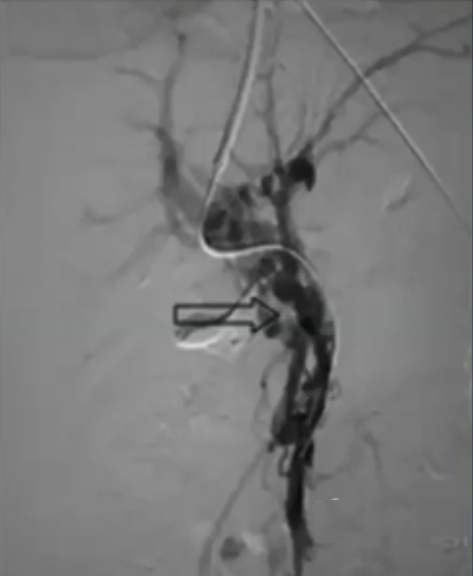

在进行门静脉血栓治疗时施行经皮穿刺取栓术所增加的额外风险主要是由于创伤所致。 从技术层面来看,要穿刺进入血栓形成的血管是相当困难的,而且有可能会反复出现成功与失败的情况。 降低风险的方法包括对静脉瓣进行成像,或者安装一个装置来引导穿刺操作。

通过经皮经脾路径具有显著优势,能够使用 4Fr 细导管和导丝进行逆向再通操作,以 10 毫米的圈套器作为经颈静脉穿刺目标,通过Avitene 完成经颈静脉门静脉穿刺。